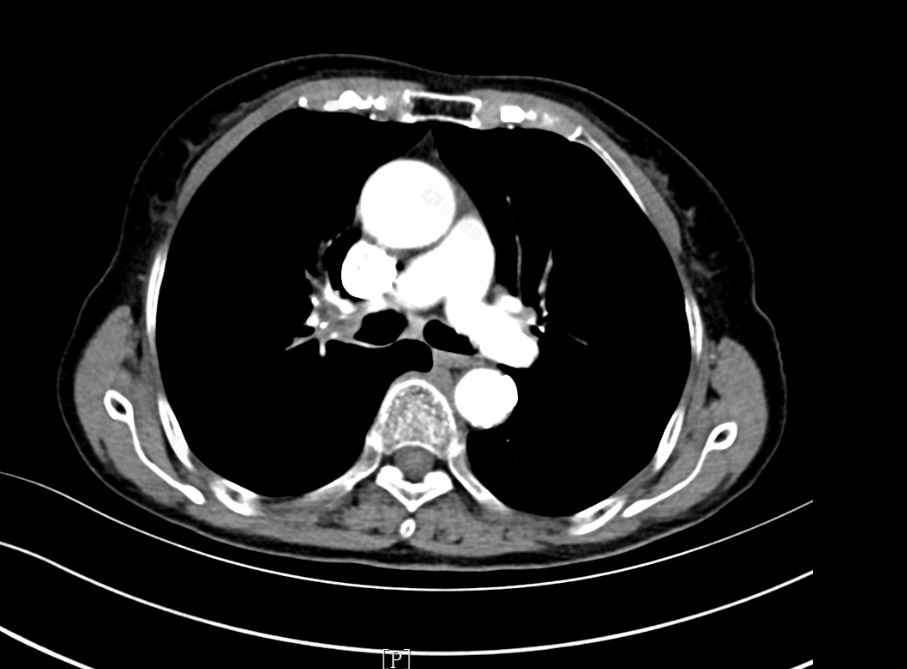

这是一个75岁的奶奶,这天她因为咳嗽咳痰症状加重并且出现了喘闷来医院就诊。患者除了以上症状之外,没有其他症状,没有头晕、头痛也没有发热、腹痛等症状。当时为患者了胸部CT检查,发现右肺门处出现占位性病变,并且双肺肺气肿、肺炎性病变,根据CT情况来看,不能排除肺恶性肿瘤的可能。因此为患者进一步进行病理检查,结果提示右肺门肿物为低分化鳞状细胞癌。属于肺癌的一种。根据患者的情况来看,建议她入院系统治疗。因此安排患者入院。

经过化疗和靶向治疗后,患者现在喘憋症状明显减轻,咳痰咳嗽的症状已经减轻,并且患者病情平稳,在治疗过程中并未出现骨髓抑制和心血管系统不适症状。复查患者CT,肿物大小未见增大,未见肿瘤转移情况,考虑疗效控制良好。